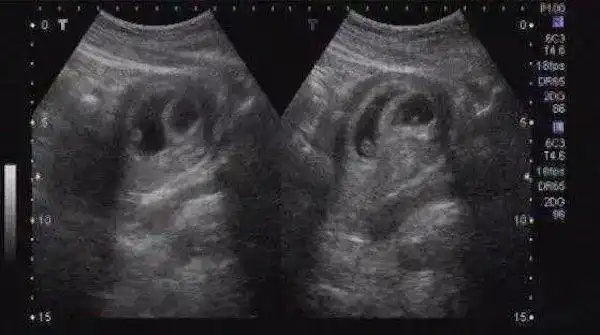

怀孕了,眼看着孕期已经3个月,但b超检查却怎么也找不到子宫里的胎儿